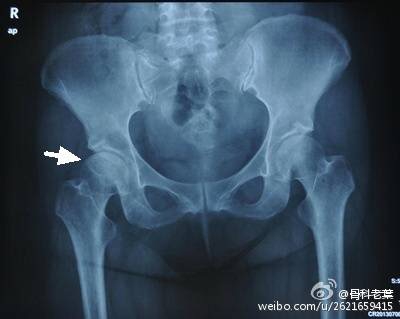

II期和III期的患者治疗方法相同,因为此时股骨头虽然还没有变形,暂时还不需要行人工关节置换术,但是股骨头已经出现空洞,随时股骨头就会塌陷变形,所以单纯的股骨头减压术是不能达到治疗效果的。这时就需要在股骨头减压的同时,植入一根支撑棒,顶住股骨头空洞区,防止股骨头在负重的情况下过早塌陷。其他治疗同之前相同,口服以上药物,定期复查,密切观察病情发展,尽量避免重体力劳动和爬山爬楼。

另附典型病例若干: